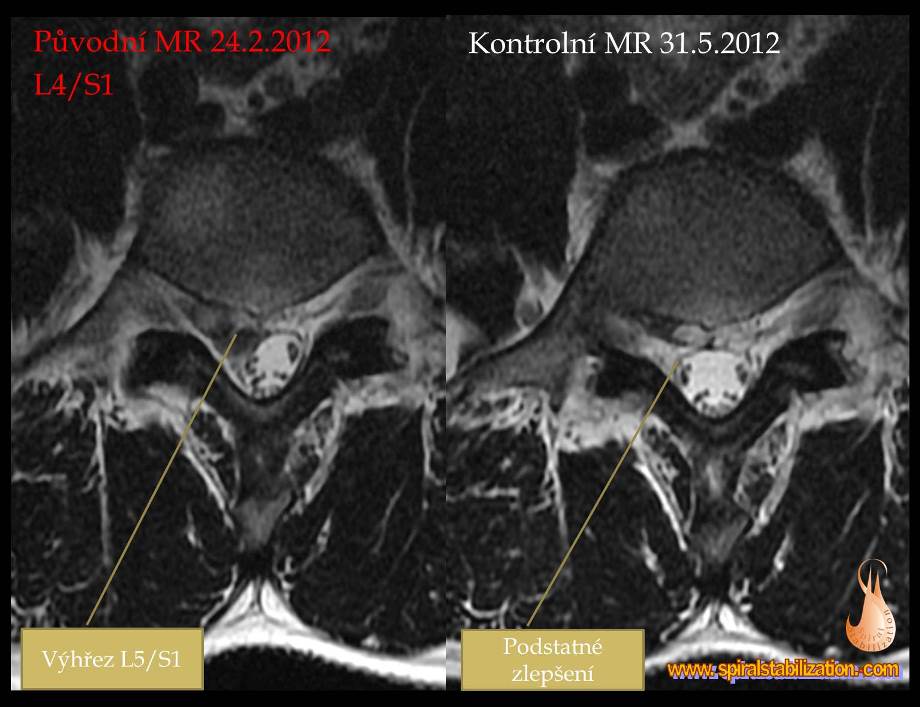

Výsledky hernia L5/S1